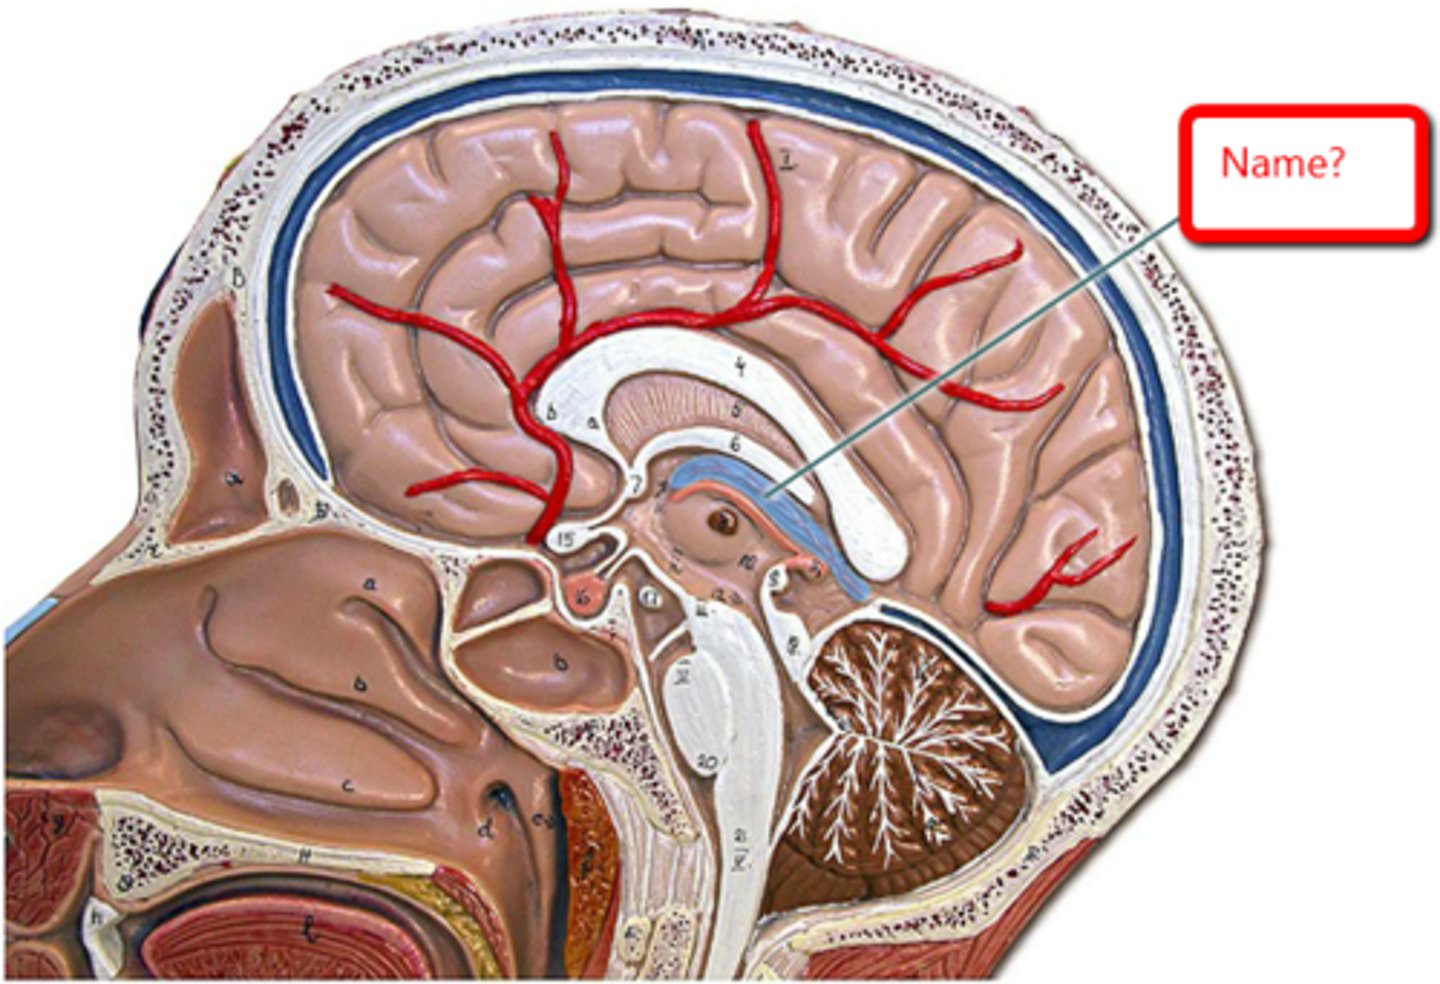

arachnoid villi

arachnoid mater of brain

dura mater of brain

pia mater of brain

falx cerebri

subarachnoid space of brain